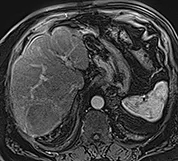

Tout d’abord une augmentation paradoxale de la taille de la tumeur peut être observée dans la phase initiale en raison de la nécrose et de l’œdème, elle est observée jusqu’à 36 % des lésions durant le 1er mois. Par conséquent, l’évaluation de la réponse tumorale doit être effectuée après 3 mois (98). La décroissance en taille de la lésion est très lente, avec une réponse complète et des critères d’amélioration qui augmentent avec le temps : dans l’étude de Lee et al., la réduction de la taille de la tumeur est de 2 % à 1 mois, 14 % à 3 mois, et 28 % à 6 mois (99). Bien que la diminution de la taille de la tumeur soit rassurante, l’absence d’augmentation dans le temps est un signe positif, et peut être considéré comme le reflet d’une réponse clinique, car l’histoire naturelle de la tumeur est la poursuite de la croissance tumorale…

Il est préférable d’utiliser les critères mRecist pour juger de l’efficacité du traitement (100), mais les variations du réhaussement tumoral, la diminution de l’hypervascularisation peuvent se faire attendre. Les données de Lee et al. montrent une amélioration selon mRecist dans 31 % des cas à 1 mois, 50 % à 3 mois et 59 % à 6 mois. Par conséquent, il faut attendre jusqu’à 3-6 mois avant de prendre la décision de retraiter, le meilleur signe de progression étant l’apparition de nouvelles lésions péritumorales ou à distance dans le foie.

La confrontation de l’analyse histologique d’explants après RE a montré que les 49 % de patients pour lesquels l’imagerie avait conclu à une réponse partielle présentaient en fait une nécrose complète histologique dans 78 % des cas, ce qui montre bien la difficulté de l’interprétation radiologique de l’imagerie de surveillance (101). Toujours dans cette étude, la présence d’un réhaussement annulaire périphérique, correspondant au tissu de granulation entourant la nécrose, était un signe de réponse positive puisque 93 % de ces lésions avec réhaussement annulaire présentaient une nécrose complète.

| Contrôle par IRM (acquisition en pondération T1 à la phase artérielle et portale) à 1 an du traitement par radiothérapie sélective interne par Therasphères dans l’artère hépatique gauche avec une dose à la tumeur de 370Gy. A noter la prise de contraste annulaire périphérique séquellaire de la lésion involuée. | |